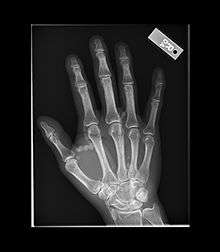

Tumoral calcinosis

Tumoral calcinosis is a rare condition in which there is calcium deposition in the soft tissue in periarticular location i.e. around joints.[1] The accumulations are outside the joint capsule. They are frequently seen in patients undergoing renal dialysis. It is also considered by some to have a hereditary predisposition. The name indicates calcinosis (calcium deposition) which resembles tumor (like a new growth). They are not true neoplasms - they don't have dividing cells. They are just deposition of inorganic calcium with serum exudate. Children and adolescents (6 to 25 years) are the most commonly affected. The symptom that the accumulations cause is not pain but swelling around joints. They have propensity to enlarge progressively and ulcerate the overlying skin and extrude. They are most common around shoulders, hips and elbows. Laboratory evaluation reveal normal serum calcium levels and hyperphosphatemia. Rarely ALP (alkaline phosphatase - an enzyme active at sites of bone formation) may be elevated. Treatment is normalization of serum phosphate levels and resection of lesion. Surgical removal should be complete and if part of it is left, there is inevitable recurrence. Cutting through the excised calcium deposition reveals semifluid calcium suspension in albumin encapsulated by fibrous tissue.